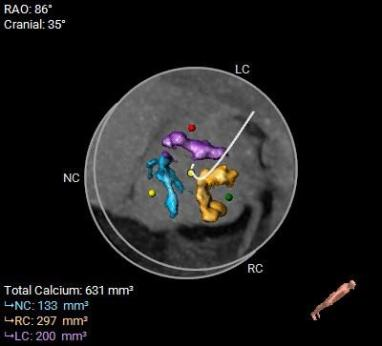

该病例主动脉根部结构较小,并且左冠脉开口高度距离瓣环较近,只有10.2mm,有一定的冠脉阻挡风险,手术团队讨论后决定在TAVR时进行冠脉保护,提前将冠脉通路准备好,并且结合球囊扩张及瓣膜释放工作位综合评估。

综合以上分析及病例特点,手术策略如下:三叶式主动脉瓣,轻度钙化伴瓣叶增厚,左冠开口较低,右冠高度可,综合瓦氏窦内径、窦管交界内径等因素考虑,左冠行冠脉保护,非横位心,弓距弓角可,左室内径可,双侧入路血管走形良好,整体入路血管条件可。计划使用20mm球囊预扩,预装23型号瓣膜,释放高度零位开始释放,最终依据术中情况决定是否做烟囱支架冠脉保护技术。

术中影像